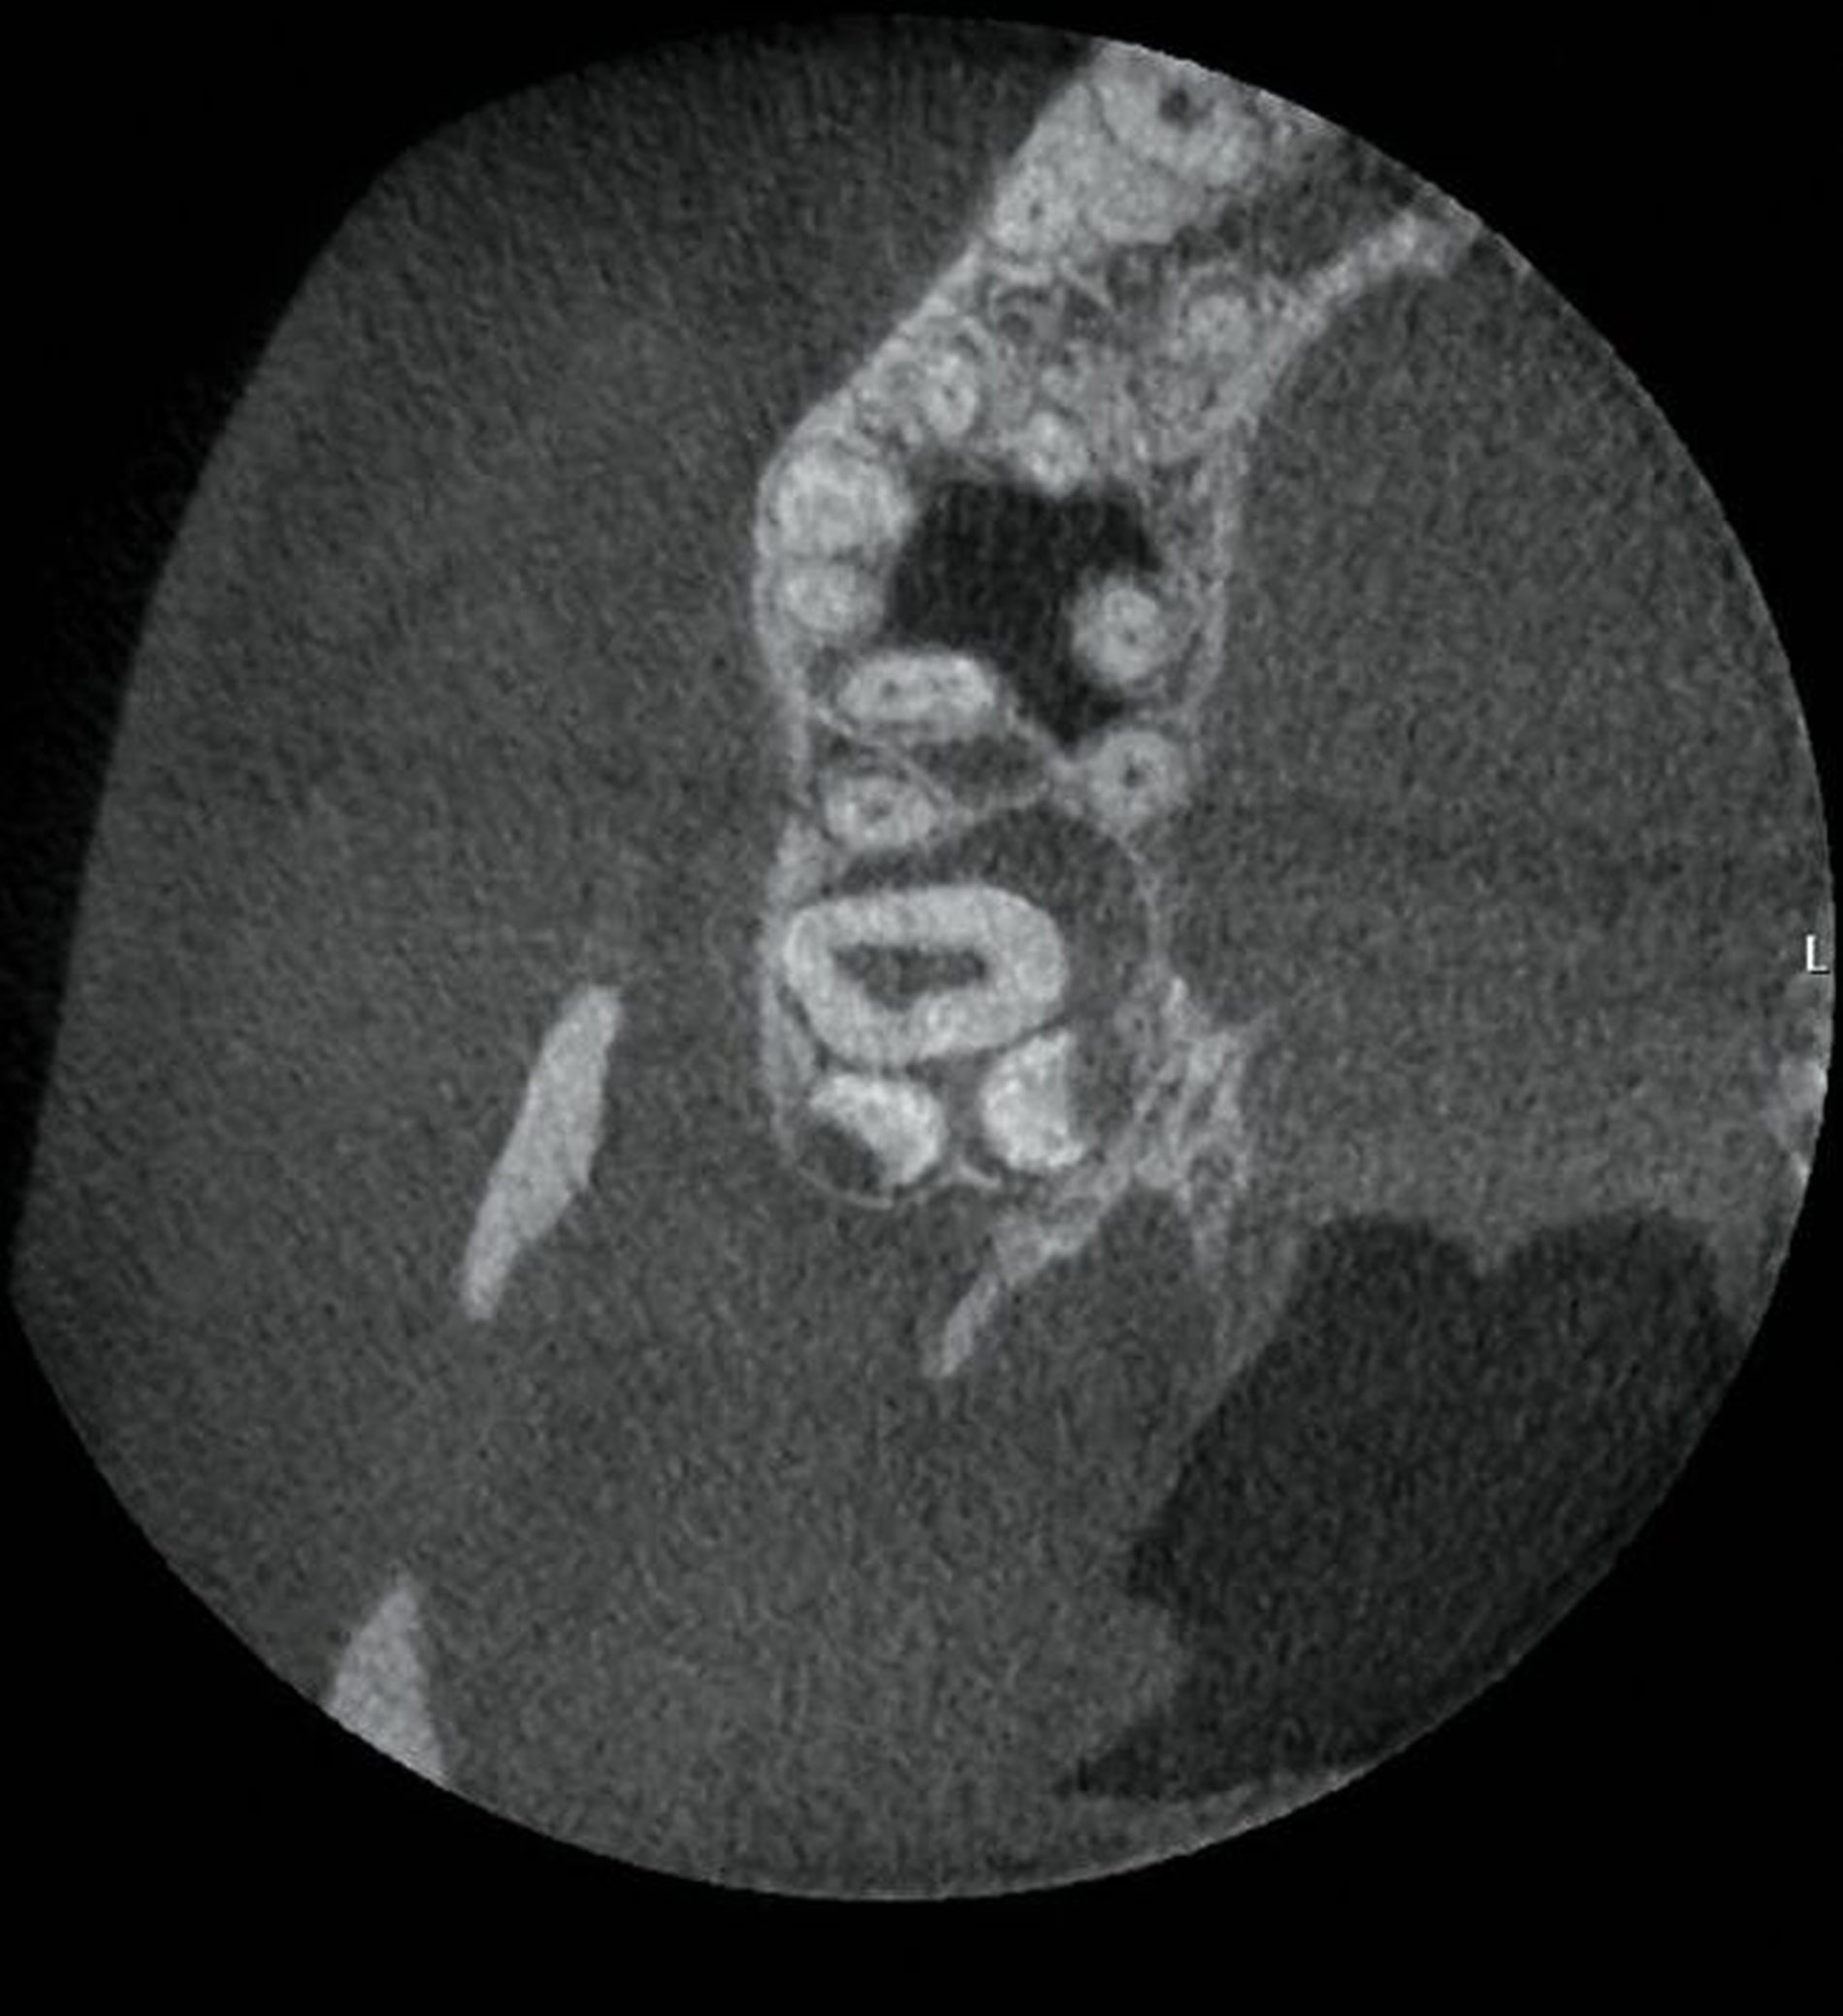

Im vorliegenden Fallbeispiel wurde eine dreidimensionale Bildgebung durchgeführt, da sowohl im Ober- als auch im Unterkiefer Risikohinweise bestanden. Zum einen lag eine unmittelbare Lagebeziehung zum N. alveolaris inferior und somit ein erhöhtes Risiko einer Nervschädigung vor, zum anderen bestanden Hinweise auf Lageanomalien und mögliche Doppelanlagen im Oberkiefer, die in der zweidimensionalen Bildgebung kaum beurteilt werden konnten. In der DVT zeigte sich in Regio 48 ein intraradikulärer Verlauf des N. alveolaris inferior durch die Wurzel des nach mesial gekippten und retinierten Zahnes 48 sowie eine perikoronare Aufhellung, die nah an die distale Wurzel des Zahnes 47 reicht (Abbildung 2).

Im Unterkiefer linksseitig zeigt sich der Canalis mandibularis lingual verlaufend, in enger Lagebeziehung zur Wurzel des retinierten und ebenfalls nach mesial gekippten Zahnes 38 (Abbildung 3).

Im Oberkiefer zeigte sich auf der linken Seite neben dem hoch verlagerten und retinierten Zahn 28 ein ebenfalls hoch verlagerter und retinierter Zahn 29 (Abbildung 4) mit enger Lagebeziehung zur Kieferhöhle. Im rechten Oberkiefer erkennt man neben dem hoch verlagerten und retinierten Zahn 18 eine Doppelanlage des Zahnes 19 ebenso in enger Lagebeziehung zur Kieferhöhle (Abbildung 5).